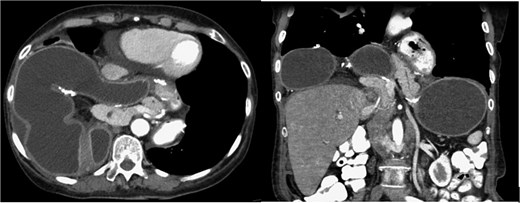

Nearly 4 years after her surgery, the patient presented to her surgeon’s clinic without any symptoms, but routine laboratory tests revealed isolated elevations in cholestatic liver enzymes. An abdominal ultrasound identified gallbladder sludge and dilation of the common bile duct to 0.9 mm, with no evidence of cholecystitis or gallstones. Additionally, a large right supradiaphragmatic fluid collection was observed. Further evaluation with computed tomography (CT) demonstrated a massive hiatal hernia containing the gastric pouch, gastrojejunal anastomosis, gastric remnant, and a portion of the pancreas (Fig. 1). The imaging also showed signs consistent with partial volvulus of the gastric remnant and associated duodenal obstruction.

CT scan—the gastric pouch, gastrojejunal anastomosis, remnant stomach, and a portion of the pancreas were located within the thoracic cavity above the diaphragm.